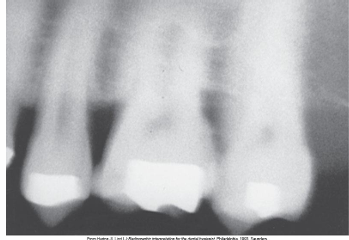

What is the problem with this OVERDEVELOPED FILM X-ray?

Appears dark, Excessive developing time, Developer solution too hot, Inaccurate timer or thermometer, Concentrated developer solution

How would you resolve this OVERDEVELOPED FILM X-ray?

Check development time • Check developer temperature • Replace faulty timer or thermometer • Replenish developer with fresh solutions as needed